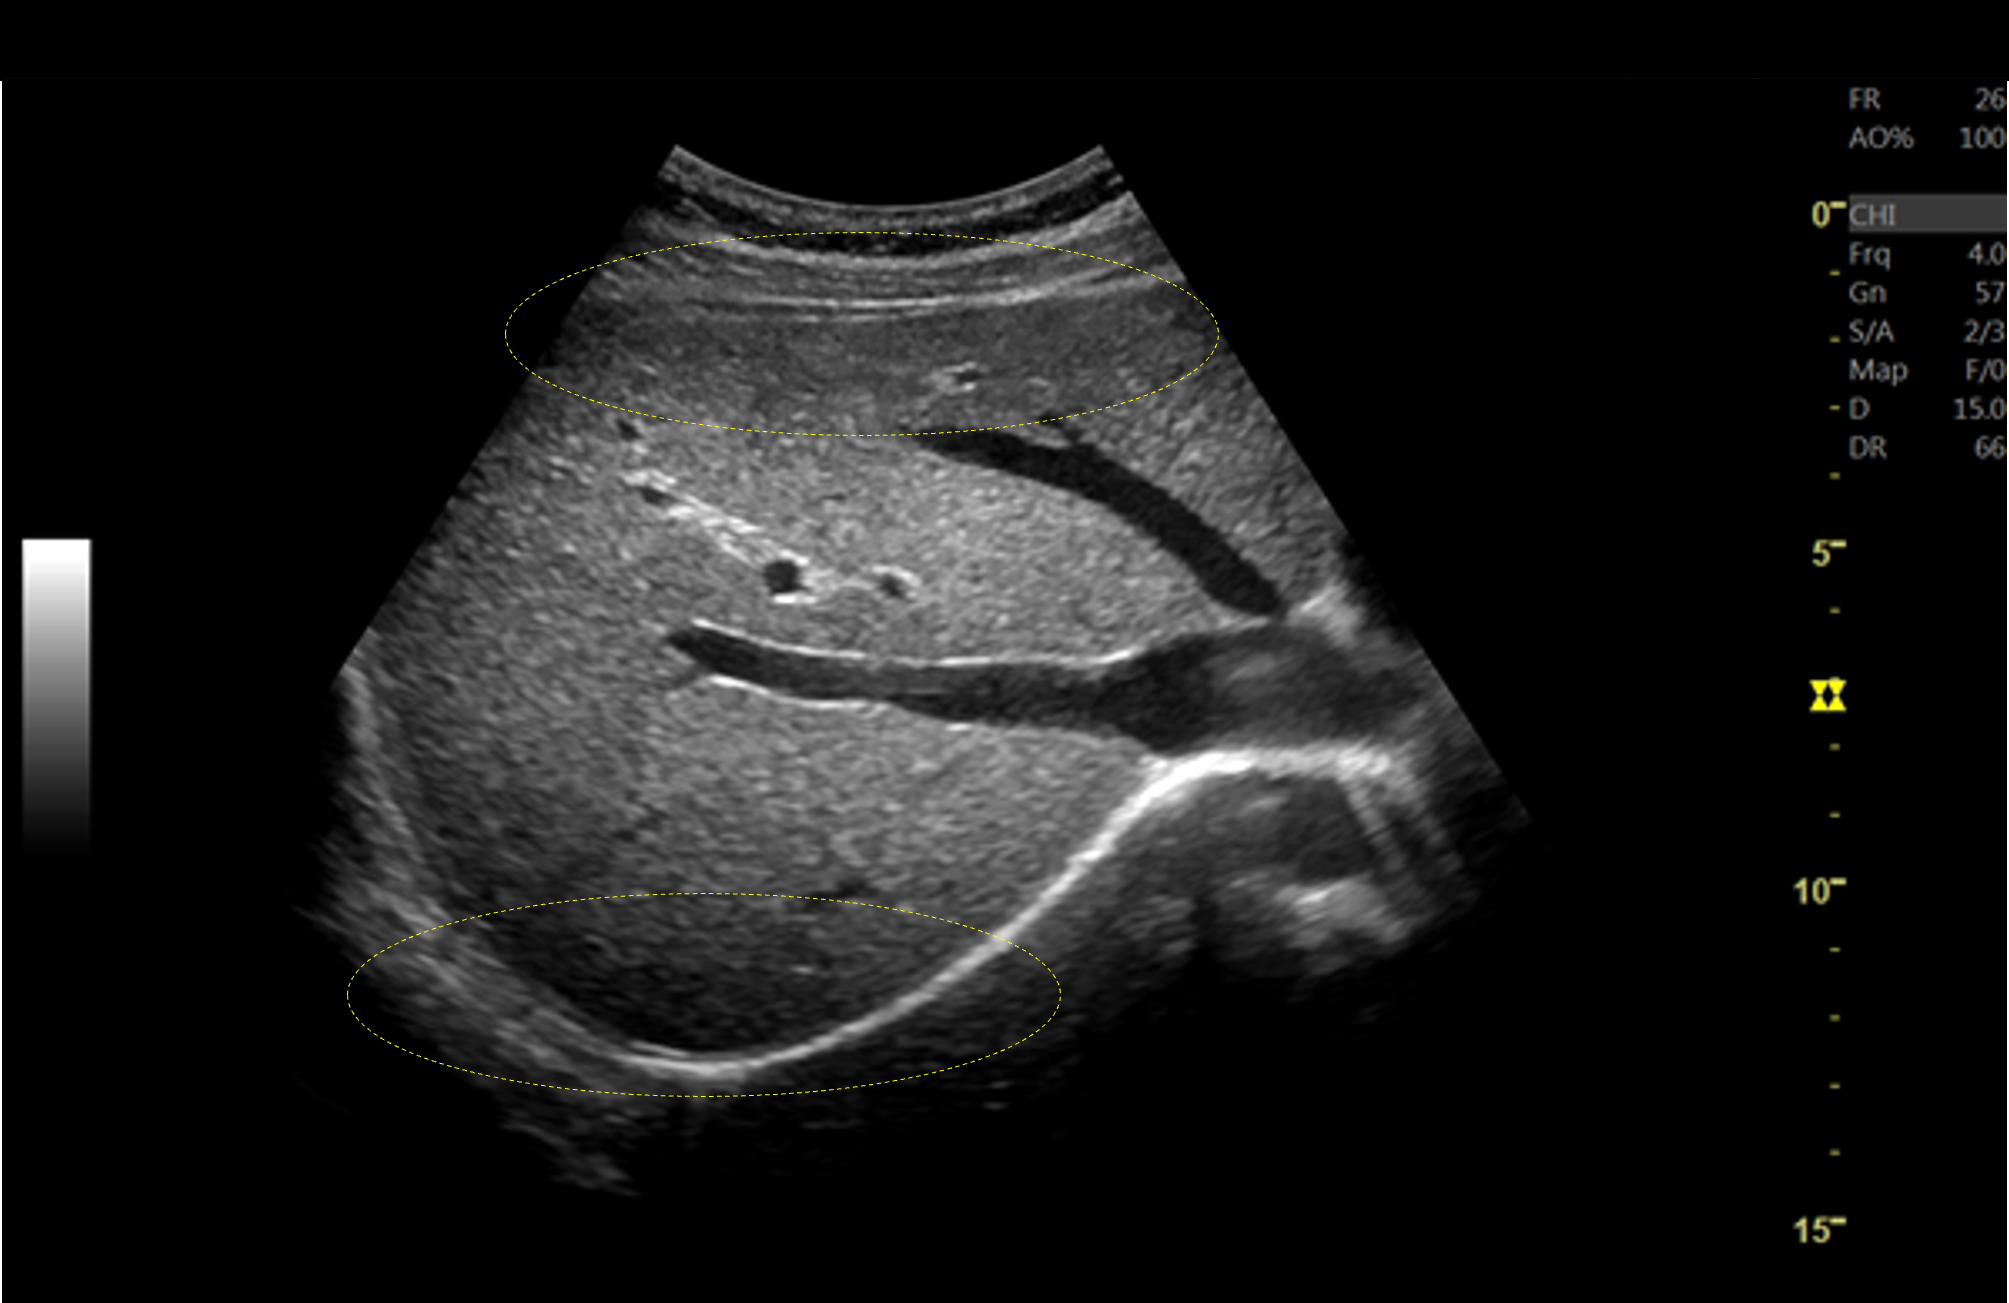

| 従来装置ではフォーカス近傍が明瞭に描出されているが、フォーカス以外の部分は明瞭に描出できておらず、関心領域に応じてフォーカスの位置を適宜変更する必要がある。LOGIQ Fortisでは、フルフォーカスにより浅部も深部も明瞭に描出され、フレームレートも高い。 |